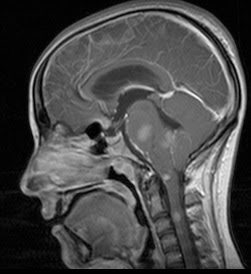

Mujer de 20 años que presenta disfonía, ptosis palpebral y pérdida de audición progresivas.

No AP conocidos.

Varón de 31 años sin AP de interés que presenta sensación de opresión y parestesias en dedos de MMII y tronco desde hacia varios meses.

En la EF se revela nistagmus horizontal y vertical.

series con gadolinio